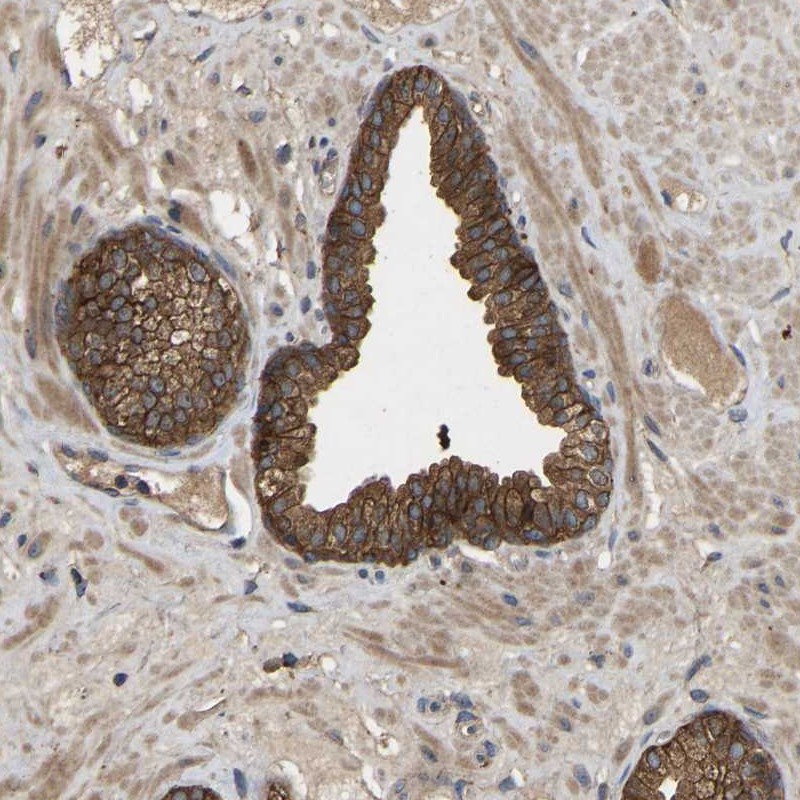

Immunohistochemical staining of human prostate shows strong cytoplasmic and membranous positivity in glandular cells.